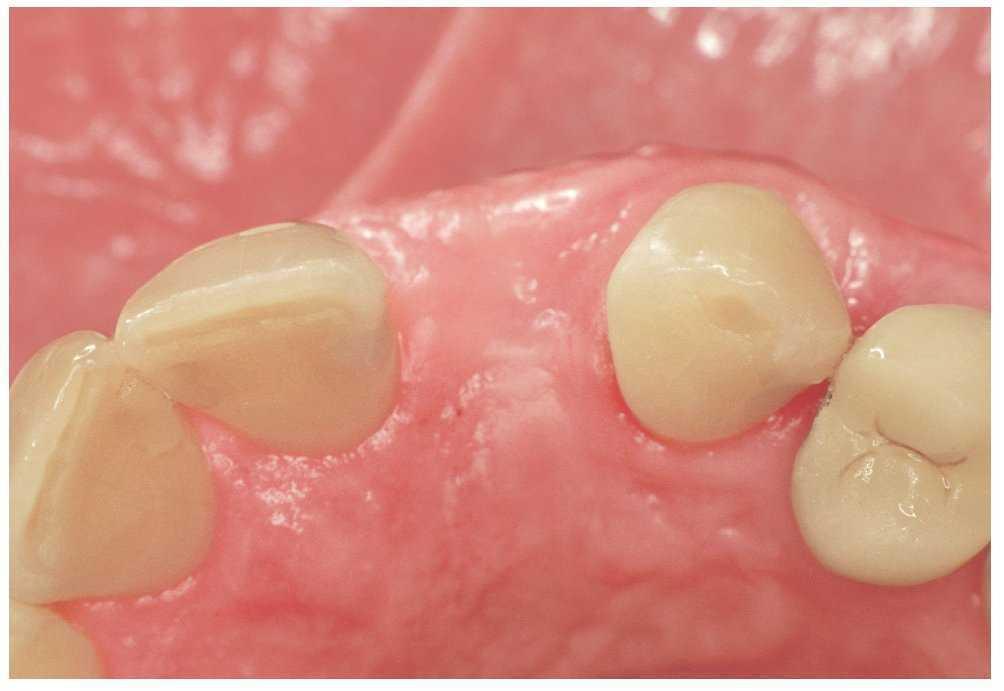

Figura 2a. Ausencia del diente 12, dientes adyacentes sin caries.

Figuras 2b y 2c. Puente adhesivo de cerámica sin metal de una aleta desde incisal (b) y vestibular (c).